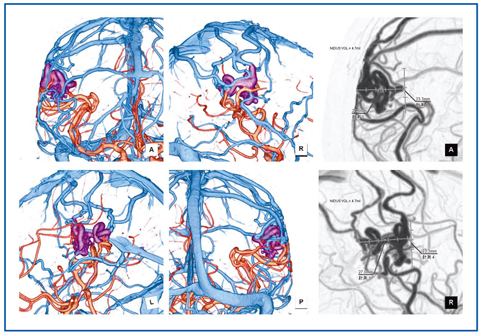

■脳動静脈奇形

MRIとともに用い、特に治療方針決定に有用である。画像処理はほぼ脳腫瘍と同様であり、脳実質や骨との解剖学的位置関係の描出や、基準線(点)とnidusの距離測定、およびnidusのおおよその大きさの算出を行う。可能な限りfeeder、nidus、drainerを分離して、色分け表示するようにしている(図7)。

図7 動静脈奇形の処理画像

複雑な血管走行になっていることが多いが、可能な限り色分け表示する。